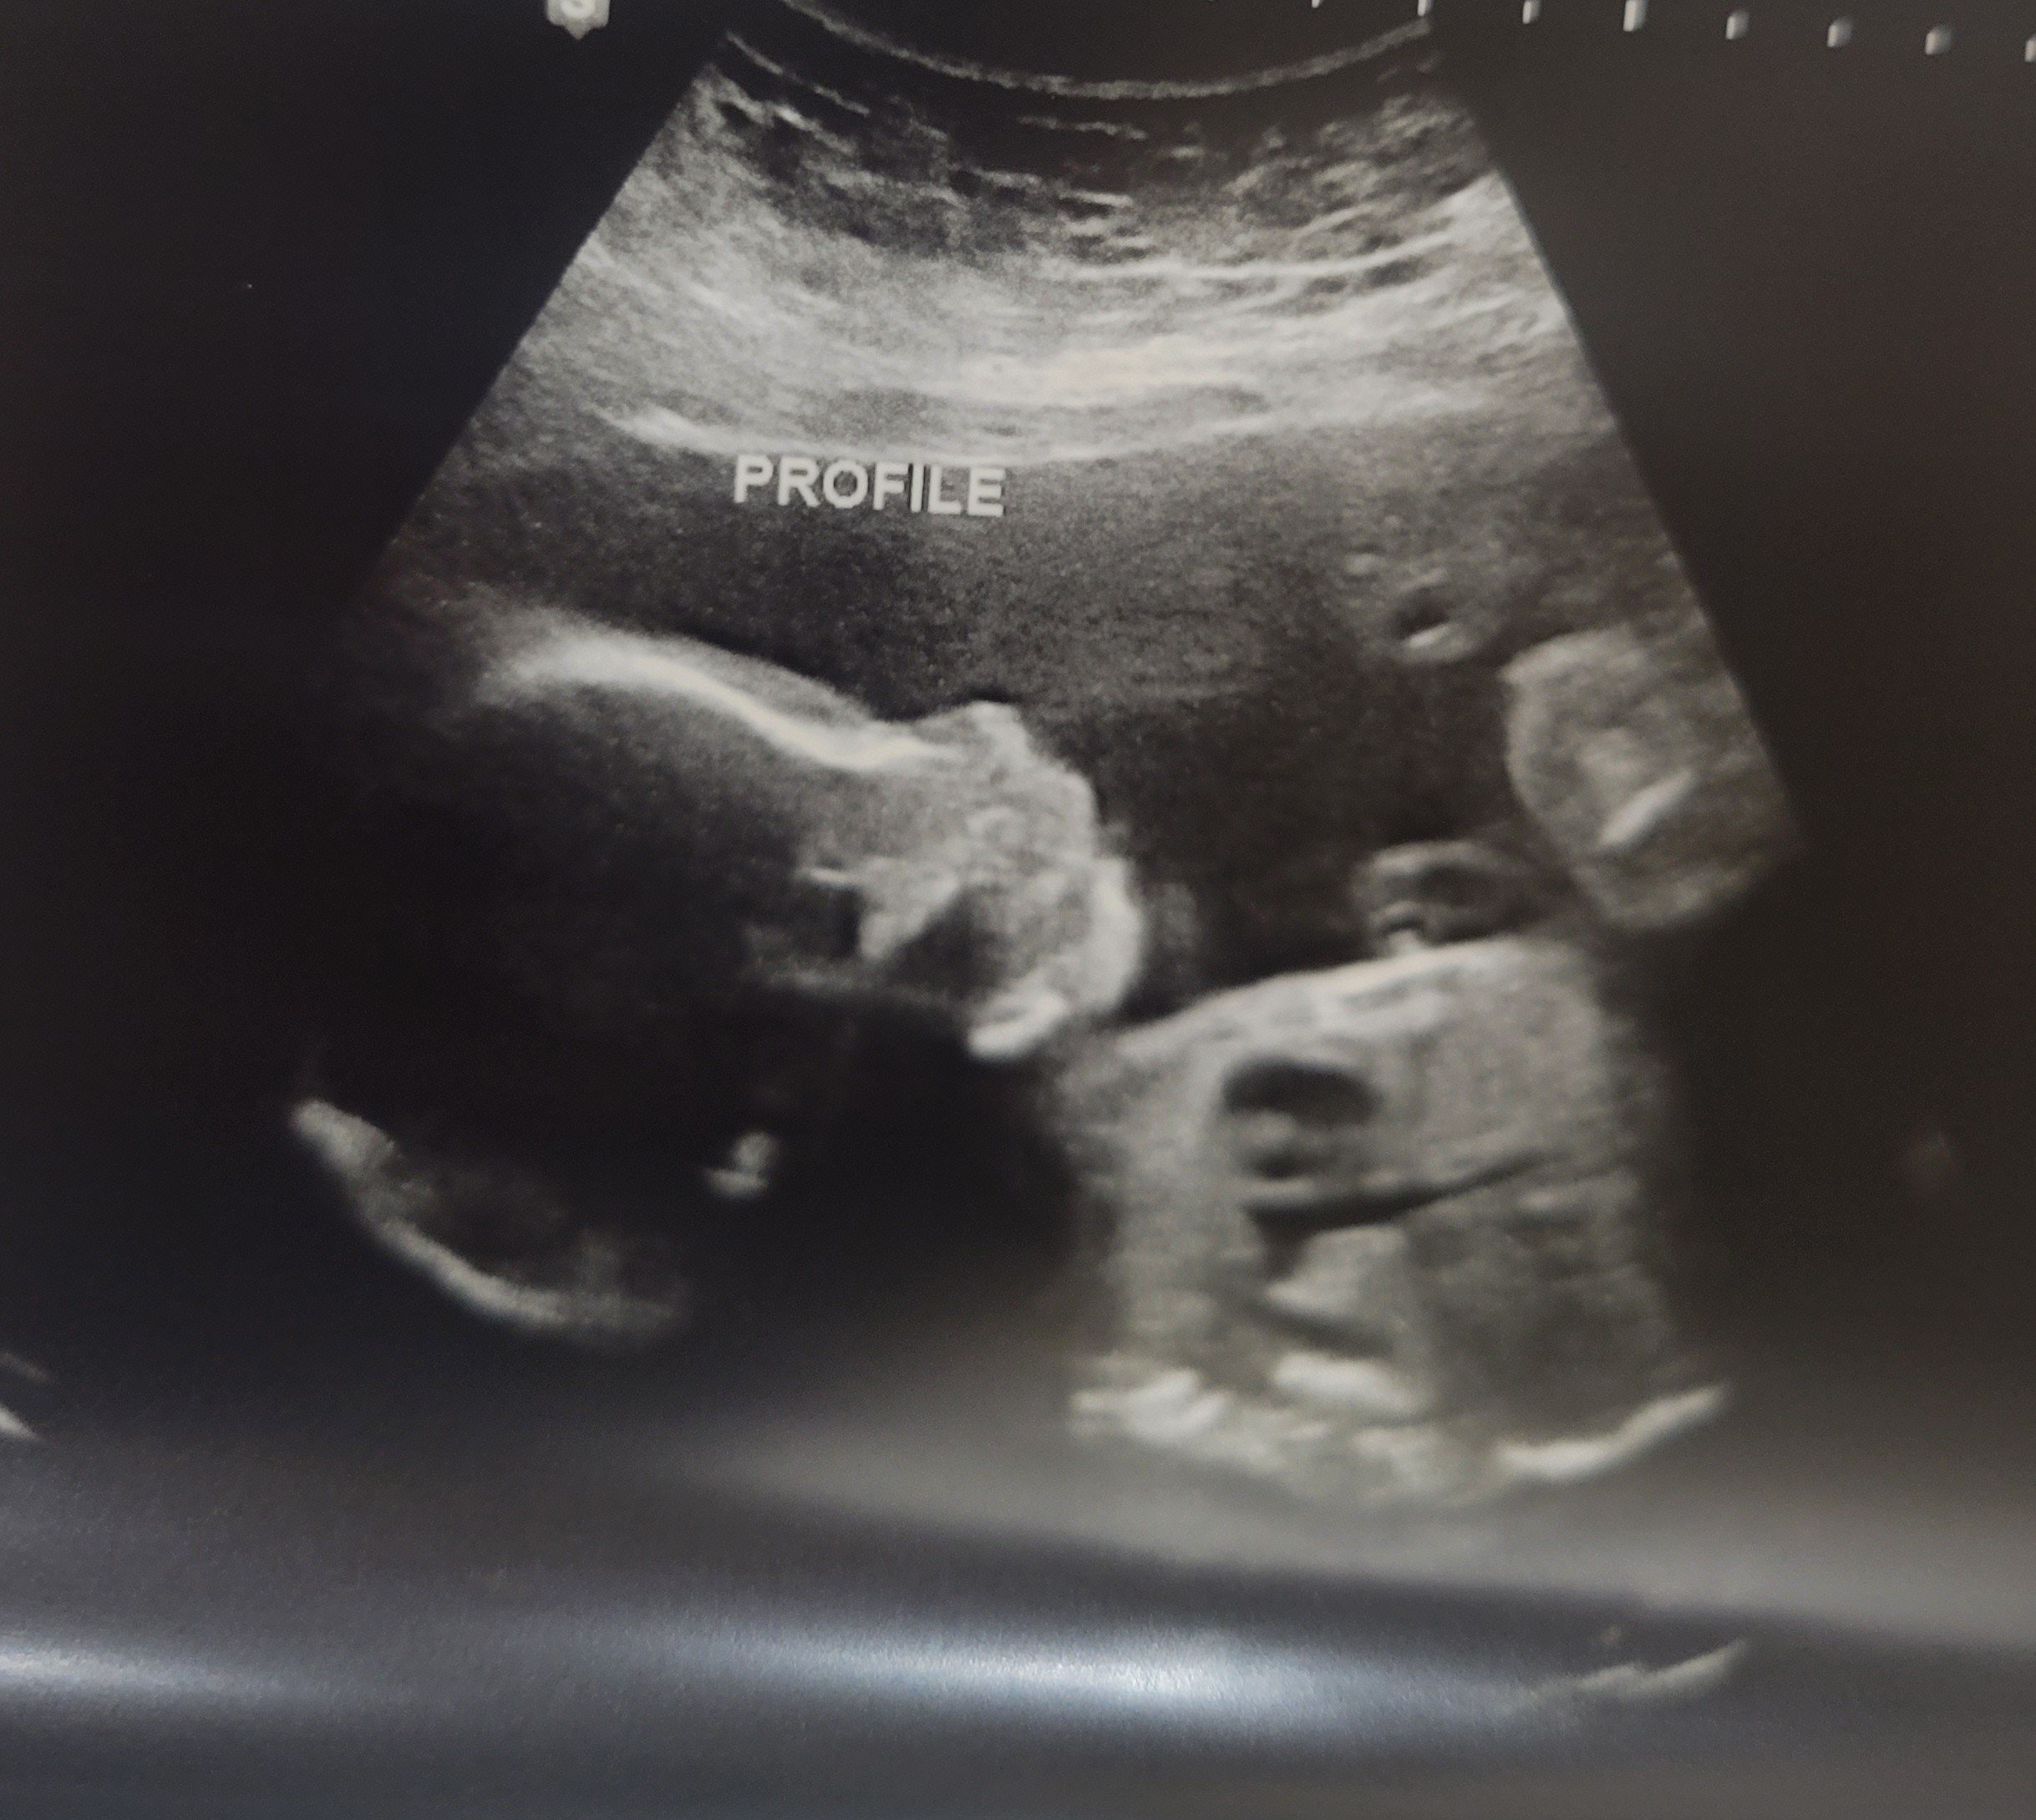

lindz42

member

June 2023

Report

4